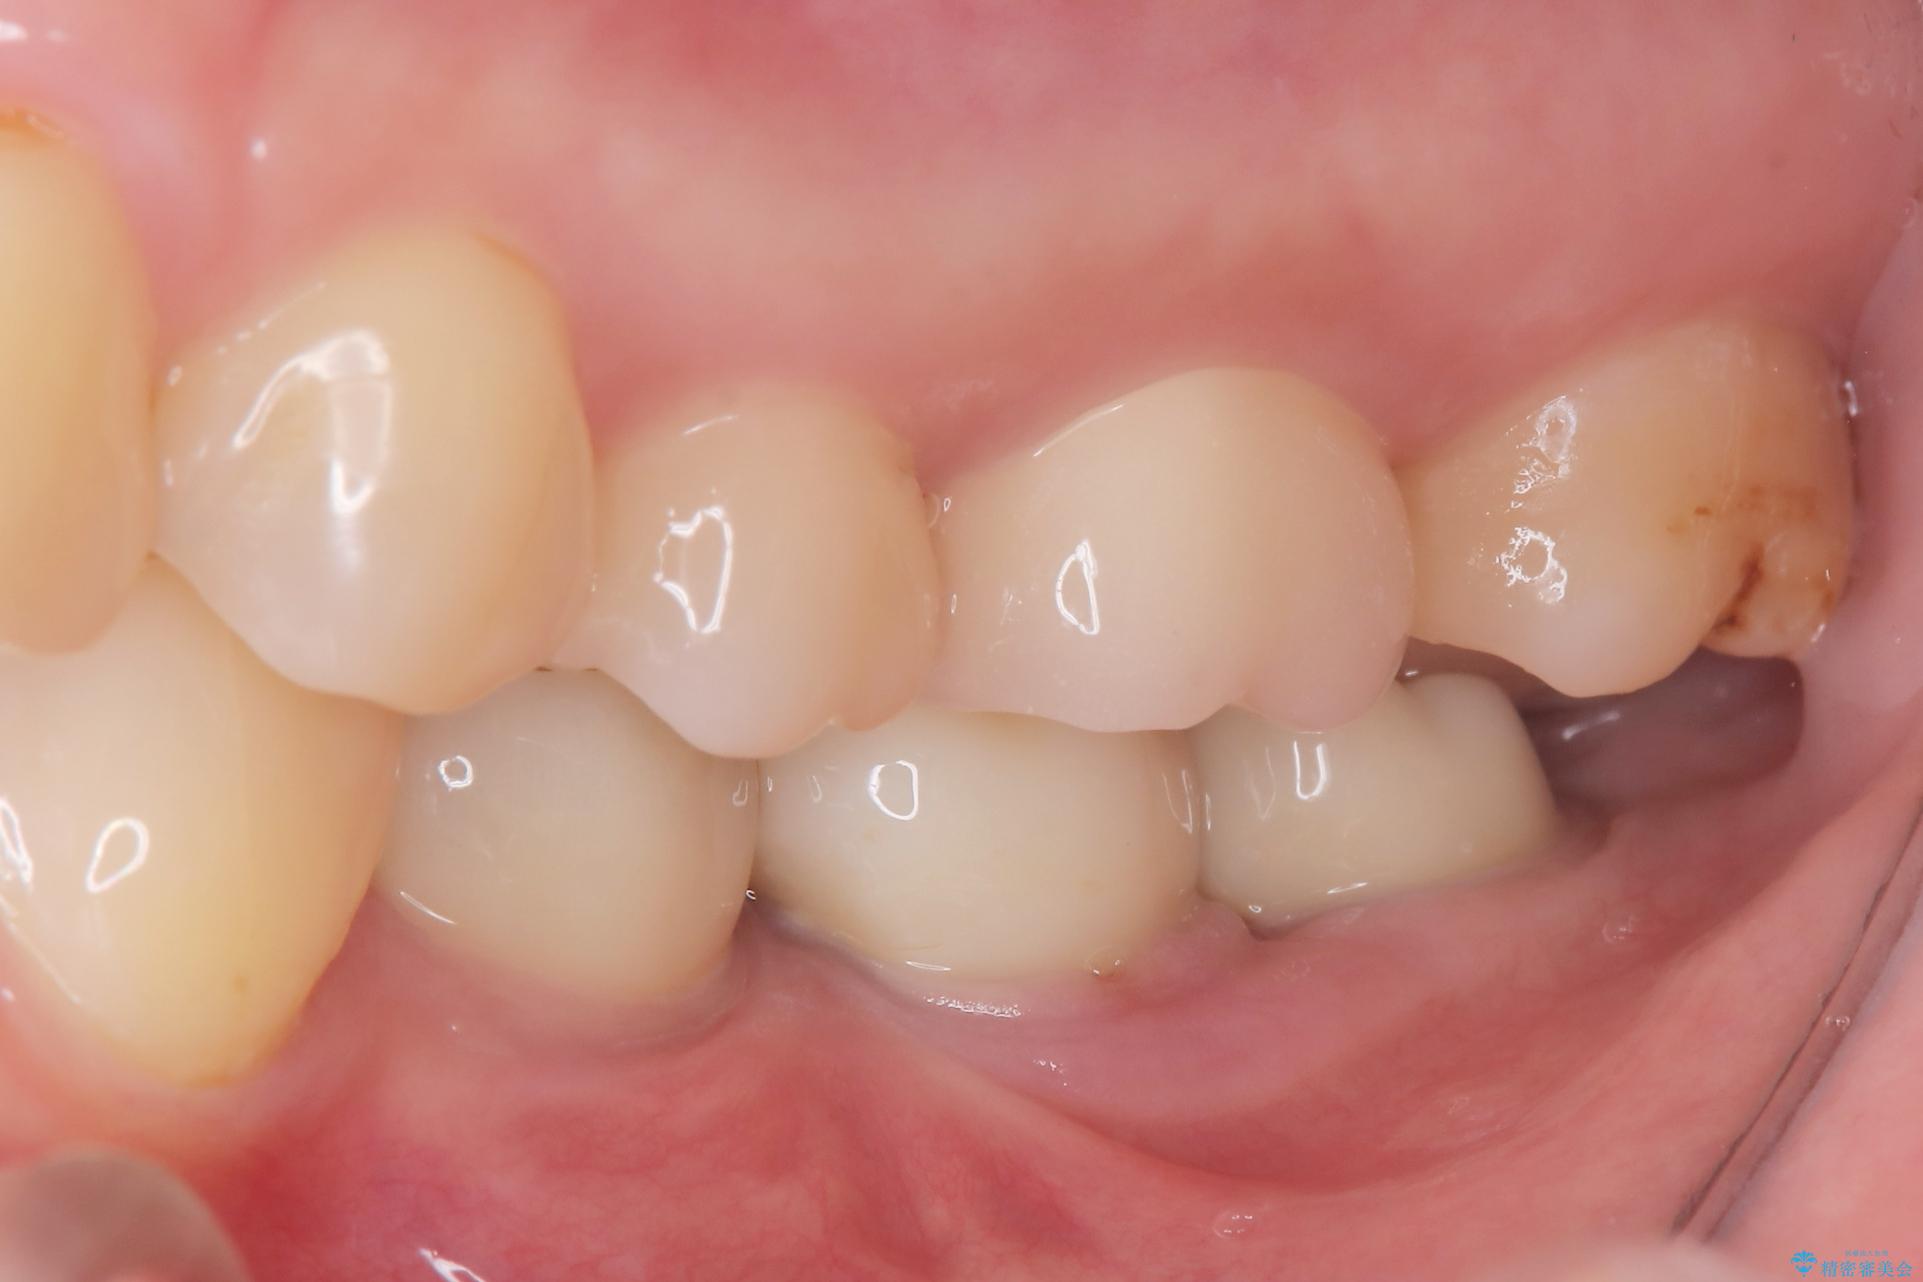

2回で完了した奥歯のセラミック修復

今回の治療では、虫歯の大きさや深さに応じて、異なるセラミック修復法を適用しました。

比較的軽度な虫歯には、セラミックインレー(詰め物)で対応し、健全な歯質を最大限に残しました。

進行した虫歯や歯の強度が低下している歯には、セラミッククラウン(被せ物)を選択し、歯全体を保護することで破折を防ぎました。

短期間での治療を可能にしつつ、天然歯と見分けがつかない審美性と、長期的に安定する機能性を兼ね備えたセラミック修復を実現しました。